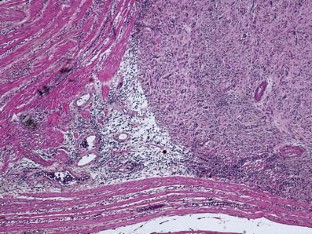

Fig. 2